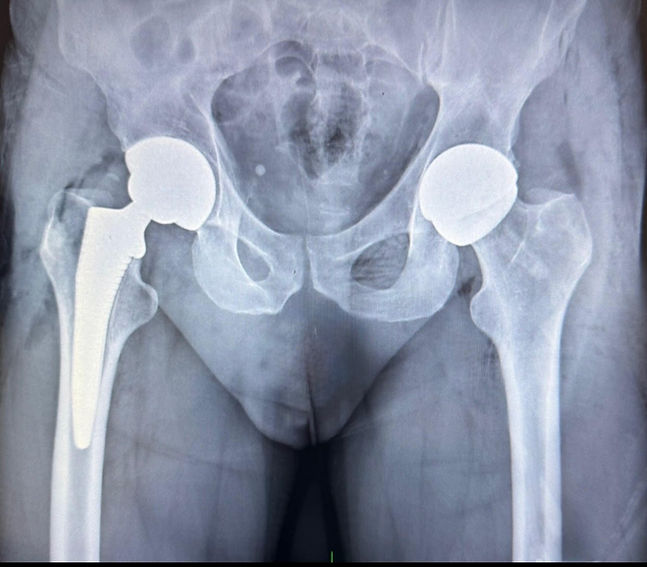

Anterior Hip Resurfacing

Hip resurfacing preserves more natural bone than a total hip replacement and is ideal for active patients who place higher demands on their joints. With modern implant options, it’s now a great option for many women as well.

Dr. Mike Millar is one of a select few surgeons in all of Australia who performs hip resurfacing through a muscle sparing, direct anterior approach that optimises recovery and function.